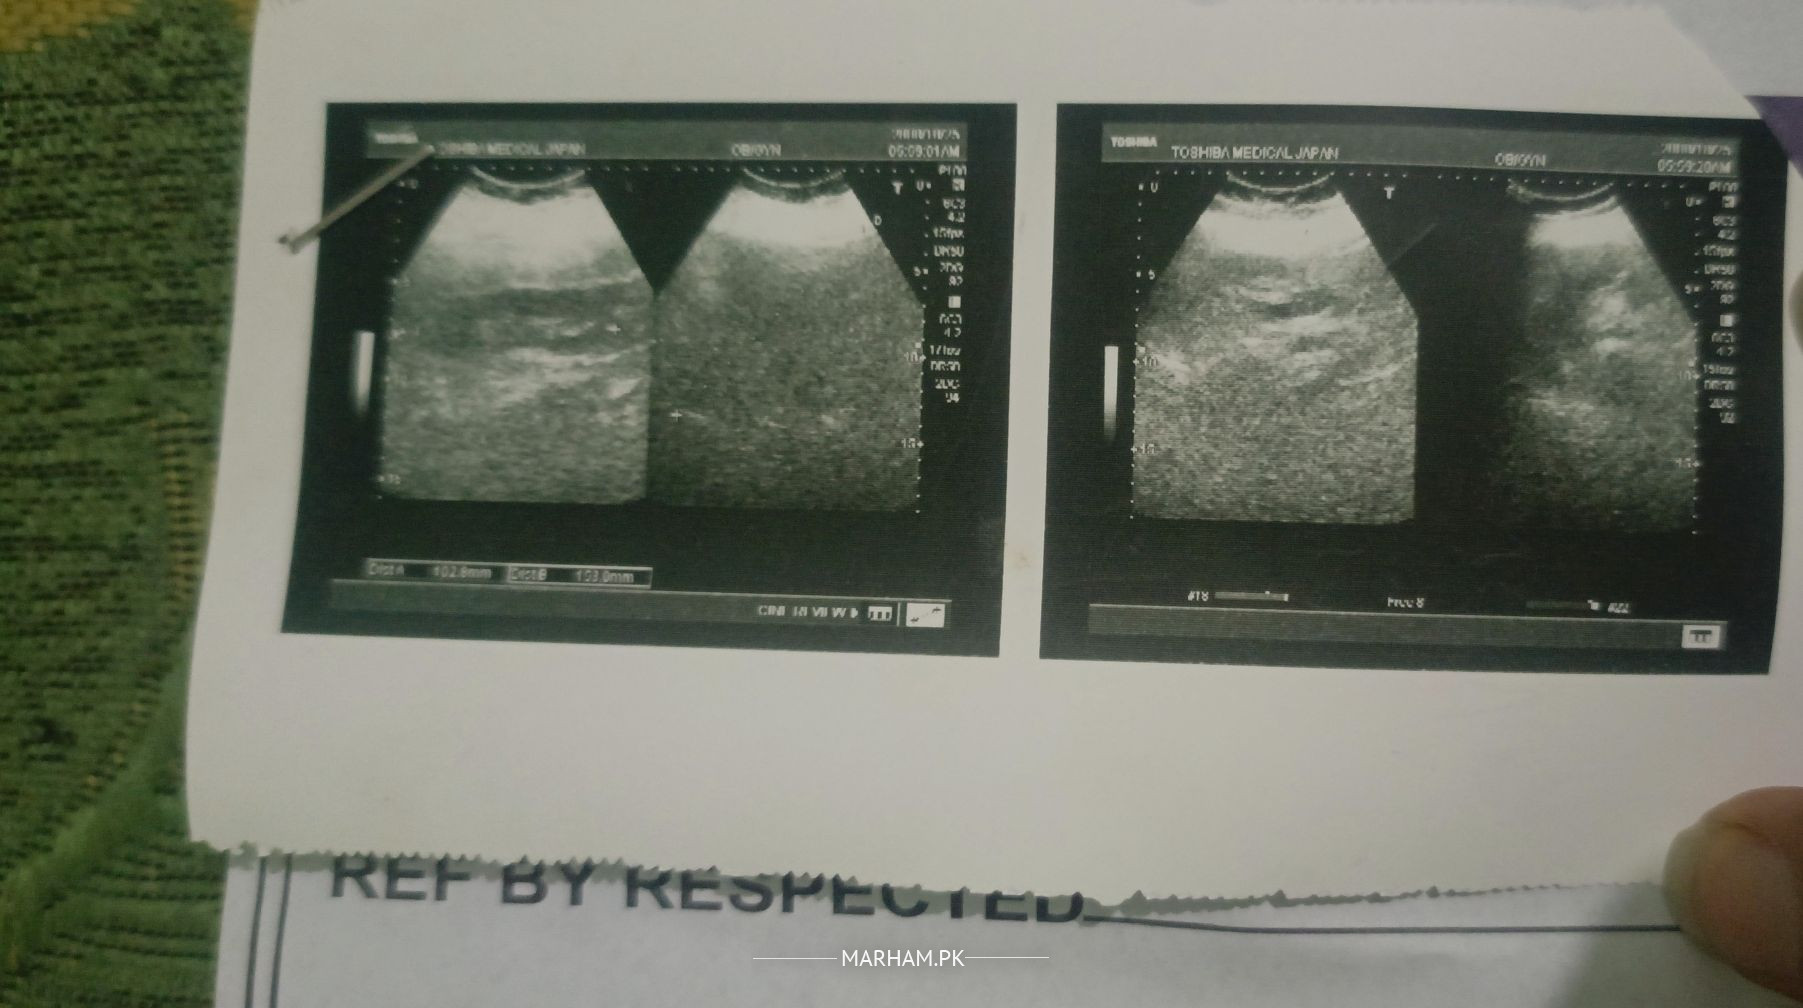

meri mother ko lower belly pr swelling feel hoti ha or pain knhu kbar hoti h lkin pain b aagy e hoti pechy wali side pr km hoti ha tu humny ultrasound b krwaya ha lkin abbi humy pta ni ha k kis doctor ko chk krwana chahiy orr kia yeh koi serious masla tu ni ha? ma sath ultraslund ki report b attach kr rhi hu kindly ap es pr guide kr skty han ?

grade 1 fatty liver hai

fatty liver means? koi kidney ka masla toh ni ha?

liver issue hai